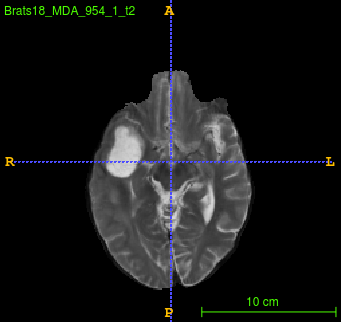

Segmentation of brain tumor from magnetic resonance imaging (MRI) is a vital process to improve diagnosis, treatment planning and to study the difference between subjects with tumor and healthy subjects. In this paper, we exploit a convolutional neural network (CNN) with hypercolumn technique to segment tumor from healthy brain tissue. Hypercolumn is the concatenation of a set of vectors which form by extracting convolutional features from multiple layers. Proposed model integrates batch normalization (BN) approach with hypercolumn. BN layers help to alleviate the internal covariate shift during stochastic gradient descent (SGD) training by zero-mean and unit variance of each mini-batch. Survival Prediction is done by first extracting features(Geometric, Fractal, and Histogram) from the segmented brain tumor data. Then, the number of days of overall survival is predicted by implementing regression on the extracted features using an artificial neural network (ANN). Our model achieves a mean dice score of 89.78%, 82.53% and 76.54% for the whole tumor, tumor core and enhancing tumor respectively in segmentation task and 67.90% in overall survival prediction task with the validation set of BraTS 2018 challenge. It obtains a mean dice accuracy of 87.315%, 77.04% and 70.22% for the whole tumor, tumor core and enhancing tumor respectively in the segmentation task and a 46.80% in overall survival prediction task in the BraTS 2018 test data set.